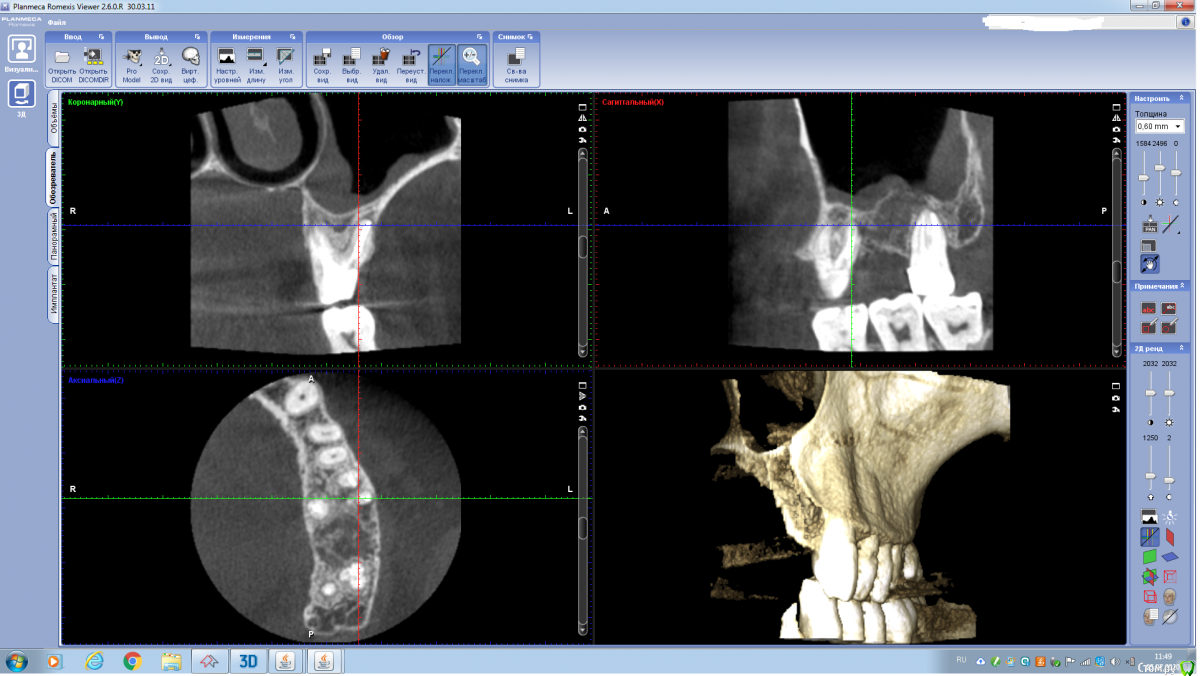

annda Опубликовано 25 июля, 2020 Поделиться Опубликовано 25 июля, 2020 (изменено) КТ до и после перелечивания.6 месяцев.Биокерамика с одиночным центральным гуттаперчевым штифтом. Изменено 25 июля, 2020 пользователем annda 2 1 Ссылка на комментарий

Redaksel Опубликовано 25 июля, 2020 Автор Поделиться Опубликовано 25 июля, 2020 КТ до и после перелечивания.6 месяцев.Биокерамика с одиночным центральным гуттаперчевым штифтом. Иванов до перелечивания.pngИванов 28.pngИванов 6 месяцев после лечения.png меня не смущает я за, начальство за такую цену нет)) Ссылка на комментарий